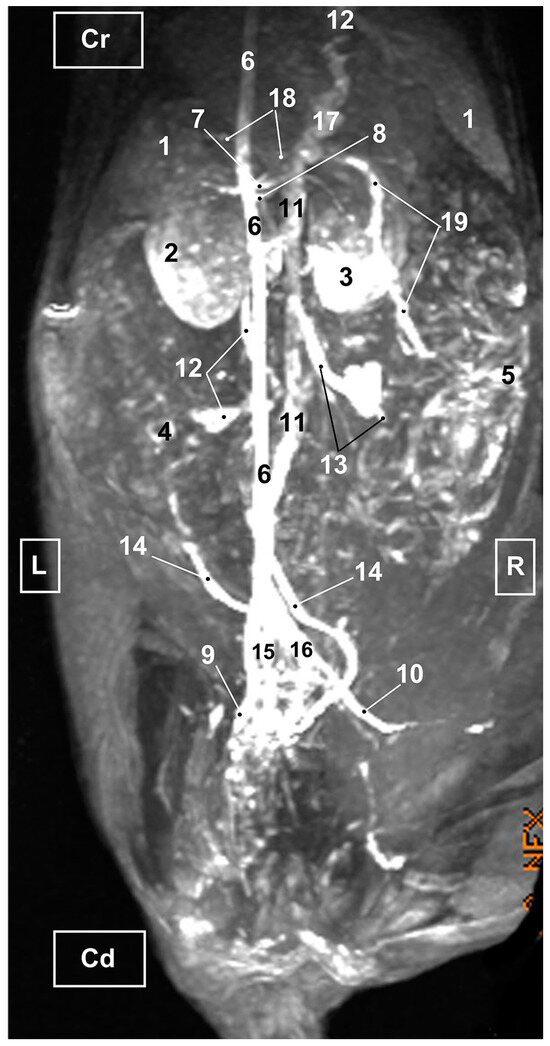

3.3. Magnetic Resonance Angiography

3.3.1. Arterial System

3.3.2. Venous System